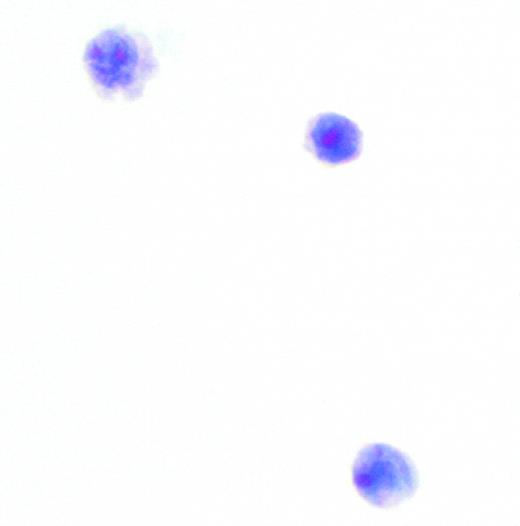

In this issue, Hegde and colleagues suggest that occult leptomeningeal disease at presentation and at relapse can be detected in high-risk patients using multicolor flow cytometry. In the newly diagnosed cohort, 11 of 51 (22%) of patients had a positive cerebrospinal fluid (CSF) by flow, yet only 1 was detected by routine cytology. The CSF fluid in these samples contained a median of only 0.002 × 109/L (2/μL) white blood cells (WBCs), and only 7% of the cells were characterized as malignant. Patients at high risk, but with negative cytology, received 12 prophylactic intrathecal therapies in addition to chemotherapy without blood-brain penetration, while the 10 with flow-positive occult disease and the 1 with a positive cytology received an intensive treatment beginning with therapy twice weekly and concluding with maintenance. In the 10 patients with follow-up at the National Institutes of Health (NIH), 7 received intrathecal via lumbar puncture and 3, via Ommaya reservoir.

This study demonstrates that flow cytometry is more sensitive than cytology in detecting occult leptomeningeal disease at diagnosis of systemic NHL with high-risk features. Importantly, Hegde et al demonstrate that 2 or more extranodal sites are the prime determinant in predicting occult or overt leptomeningeal disease, a factor commensurate with the biology of the disease. However, are these results widely applicable and should all patients deemed to be at risk have CSF sent for flow cytometry? It is certainly notable that 45% of the patients in this study had HIV, although only 64% of those with positive CSF fluid had HIV. Consequently, a prospective multi-institutional study in both HIV-positive and -negative individuals would prove that this approach can be generalized. It would also help answer the question as to whether aggressive intrathecal therapy can be more efficacious in those with flow-positive CSF if given via Ommaya or if agents with longer half-lives such as rituximab or liposomal cytarabine are used.FIG1 ▪